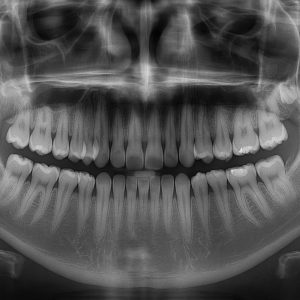

Ako tražite 2D snimanje zuba u Beogradu, Dental Scan nudi najmoderniju dijagnostiku sa ultra HD kvalitetom slike i minimalnom dozom zračenja. Naši digitalni 2D snimci pružaju jasan prikaz svih zuba, vilica, viličnih zglobova i okolnih struktura – u samo nekoliko sekundi i bez zakazivanja.

- Za otkrivanje skrivenih problema – karijes, ciste, zapaljenja

Vrste 2D snimanja u Dental Scan centru